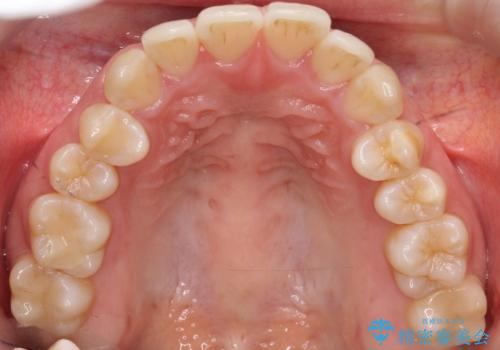

- 口元をさげたいという主訴で来院されました。4番の歯を4本抜歯し、審美装置にて治療をしました。

抜歯をしたことで口元の突出感が改善しました。約2年を予定していた矯正ですが、約1年という短い期間で終了できました。